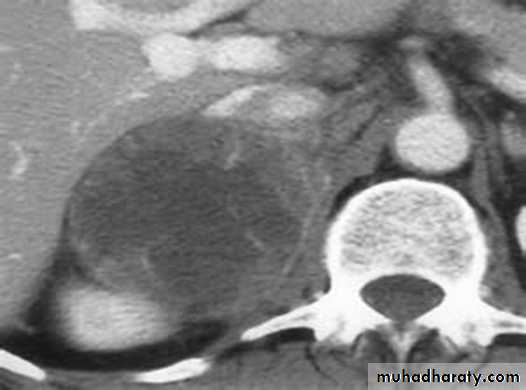

Approximately 60% of patients present with evidence of steroid hormone excess (Cushing’s syndrome). Patients with nonfunctioning tumours complain of abdominal or back pain caused by large tumours.Diagnosis

3-MRI and CT are equally effective in distinguishing adrenocortical adenoma from carcinoma .